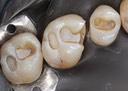

Joe Cha #18 amalgam removal

Joe Cha #18 prep